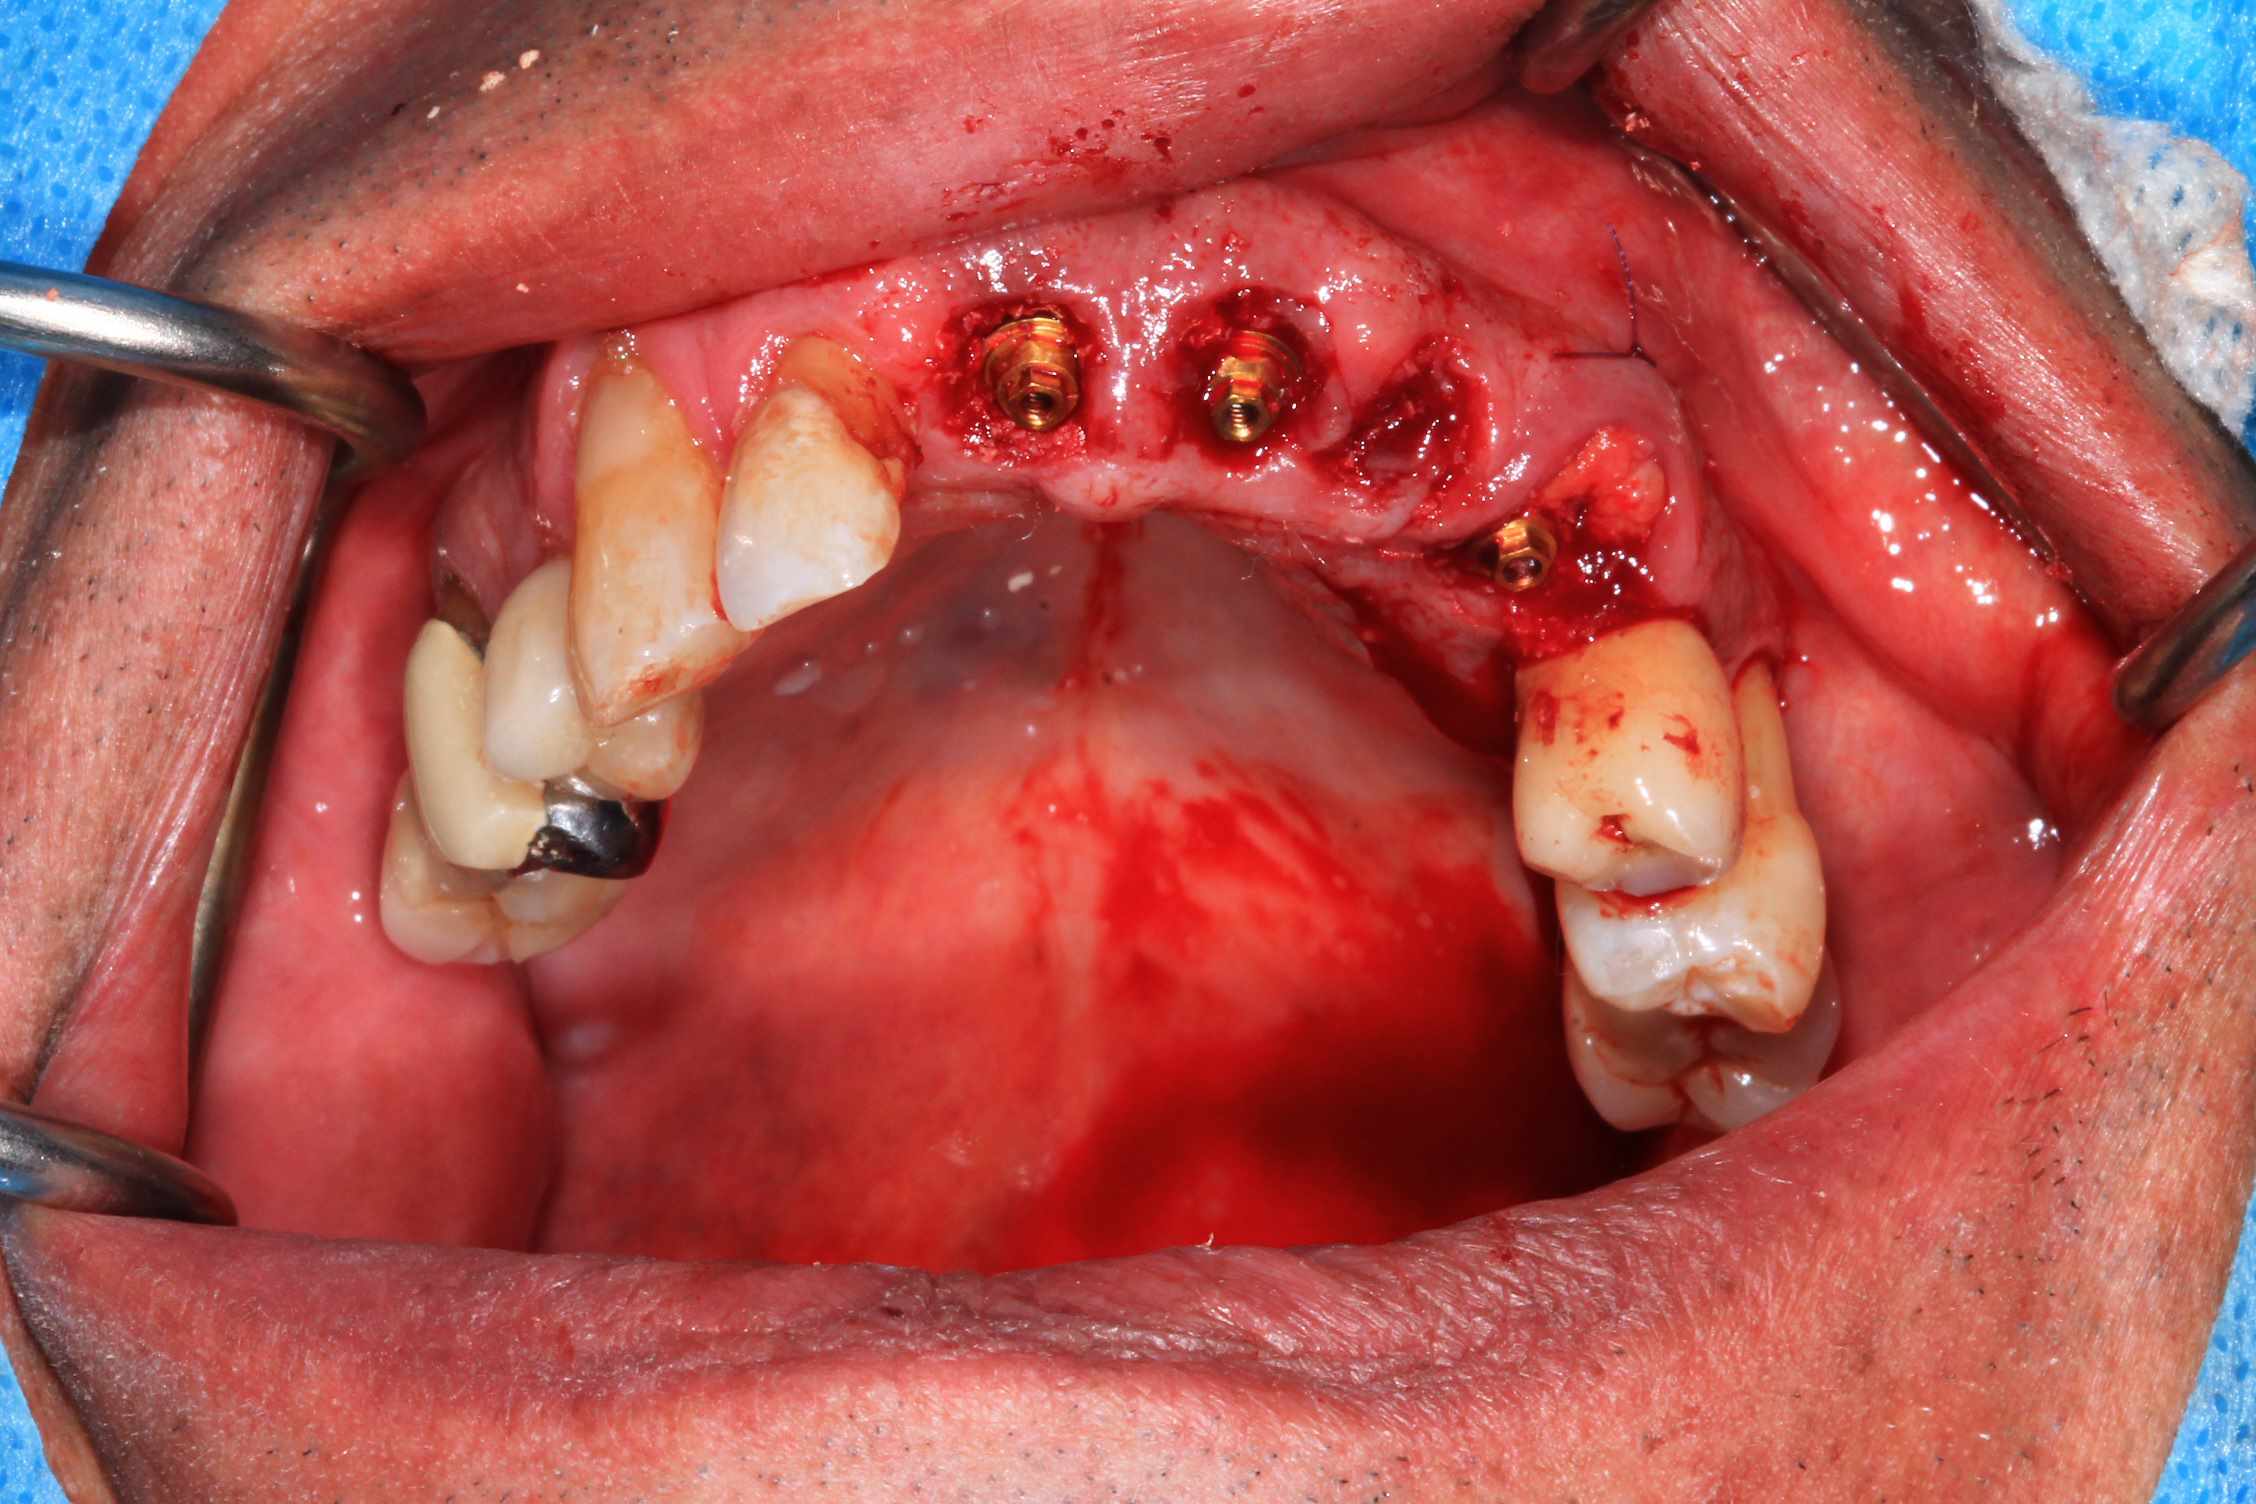

Mais celui la est tout chaud ( de vendredi dernier ) et j'ai regarder le temps que j'ai mis ( beaucoup plus complexe, donc plus long ). on va l'appeller Cas 2.

3 h de planif, modélisation du guide, puis 2 h environ pour la simulation de la chir , le modelisation et l'impression du bridge, qui tombe pile, zero retouche occlusale.

Avec un plan de traitement qui est suceptible de débat :)

Cas 2 , suite : avec une saussage au passage..

le patient arrive a 9 h, Prise de sang, PRF, injection de corticoïde, anesthésie et installation au bloc. Premier coup de bistouri a 9h30. Dernière suture a 11h30.